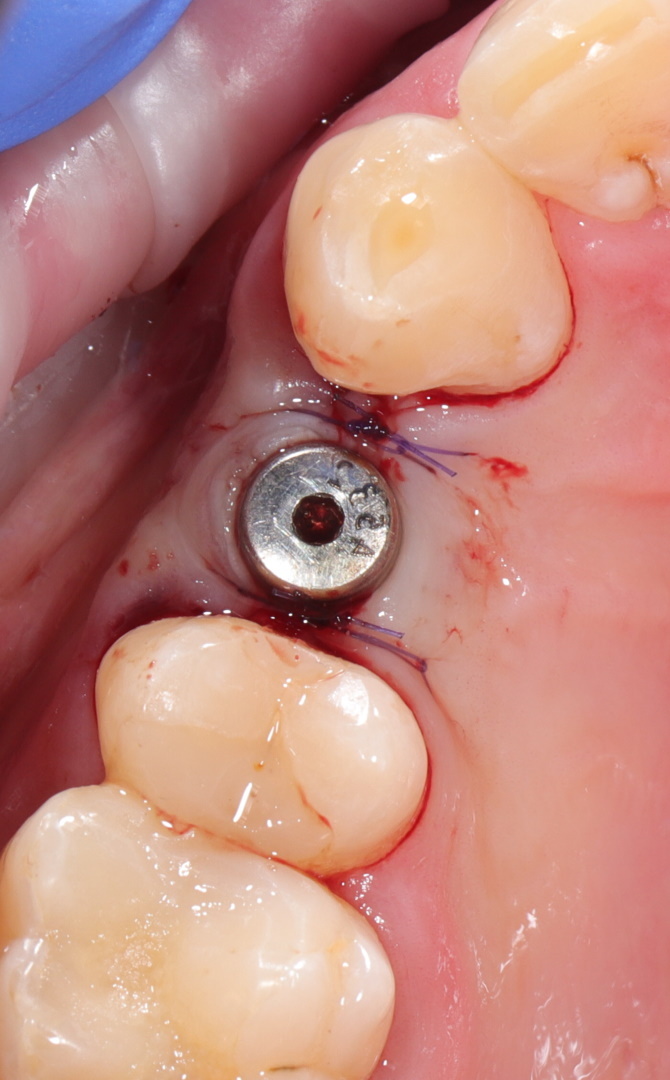

Ранее удаленный зуб 36 - незначительная атрофия по костным тканям и довольно выраженная атрофия по мягким тканям.

Имплант Straumann BLT 4.1*8mm SLActive - установлен в субкрестальное положение, произведено профилирование кортикальной кости системой Straumann Bone Profiler с целью создания более выгодного профиля прорезывания и исключения костной резорбции в области шейки импланта.

Чтобы компенсировать недостаточный объем мягких тканей проведена - мягкотканая пластика деэпителизированным соединительнотканным трансплантантом с неба.

Установлен заживляющий абатмент диаметром 6.5 мм.

Обратите внимание на объем и качество мягких тканей в области будущей финальной реставрации!

Финальная реставрация и диоксид циркония в полную анатомию методом раскрашивания.

Резюме:

Этот кейс мы с Сергеем смело относим к разряду простых - но, если посмотреть на него внимательно - здесь на каждом этапе есть определенные нюансы начиная от разреза и заканчивая финальной реставрацией.